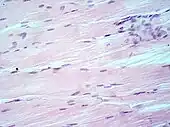

H&E is the combination of two histological stains: hematoxylin and eosin. The hematoxylin stains cell nuclei a purplish blue, and eosin stains the extracellular matrix and cytoplasm pink, with other structures taking on different shades, hues, and combinations of these colors.[5][6] Hence a pathologist can easily differentiate between the nuclear and cytoplasmic parts of a cell, and additionally, the overall patterns of coloration from the stain show the general layout and distribution of cells and provides a general overview of a tissue sample's structure.[7] Thus, pattern recognition, both by expert humans themselves and by software that aids those experts (in digital pathology), provides histologic information.

Hematoxylin principally colors the nuclei of cells blue or dark-purple,[6][15][14] along with a few other tissues, such as keratohyalin granules and calcified material. Eosin stains the cytoplasm and some other structures including extracellular matrix such as collagen[5][7][14] in up to five shades of pink.[8] The eosinophilic (substances that are stained by eosin)[5] structures are generally composed of intracellular or extracellular proteins. The Lewy bodies and Mallory bodies are examples of eosinophilic structures. Most of the cytoplasm is eosinophilic and is rendered pink.[10][15] Red blood cells are stained intensely red.